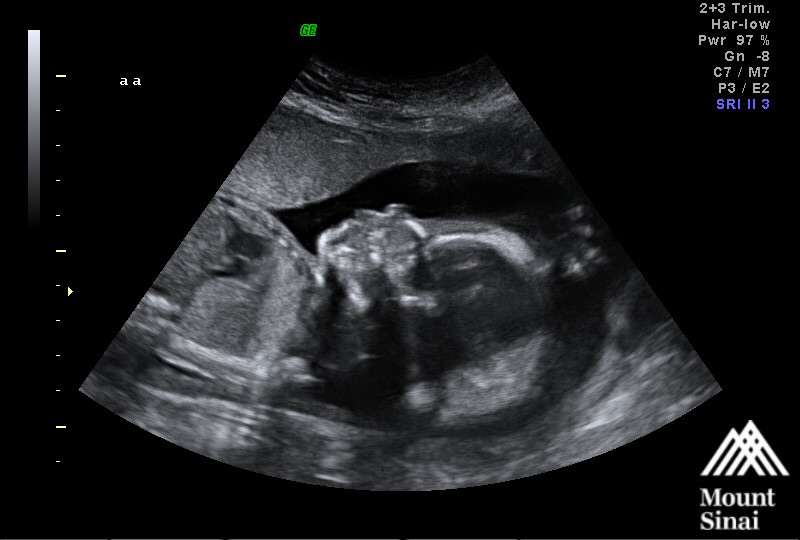

23 weeks! Please excuse my sloppiness, Im battling a nasty cold. That was the best I could do! U/S is from our Echocardiogram on Monday. Baby girl's heart looks perfect!